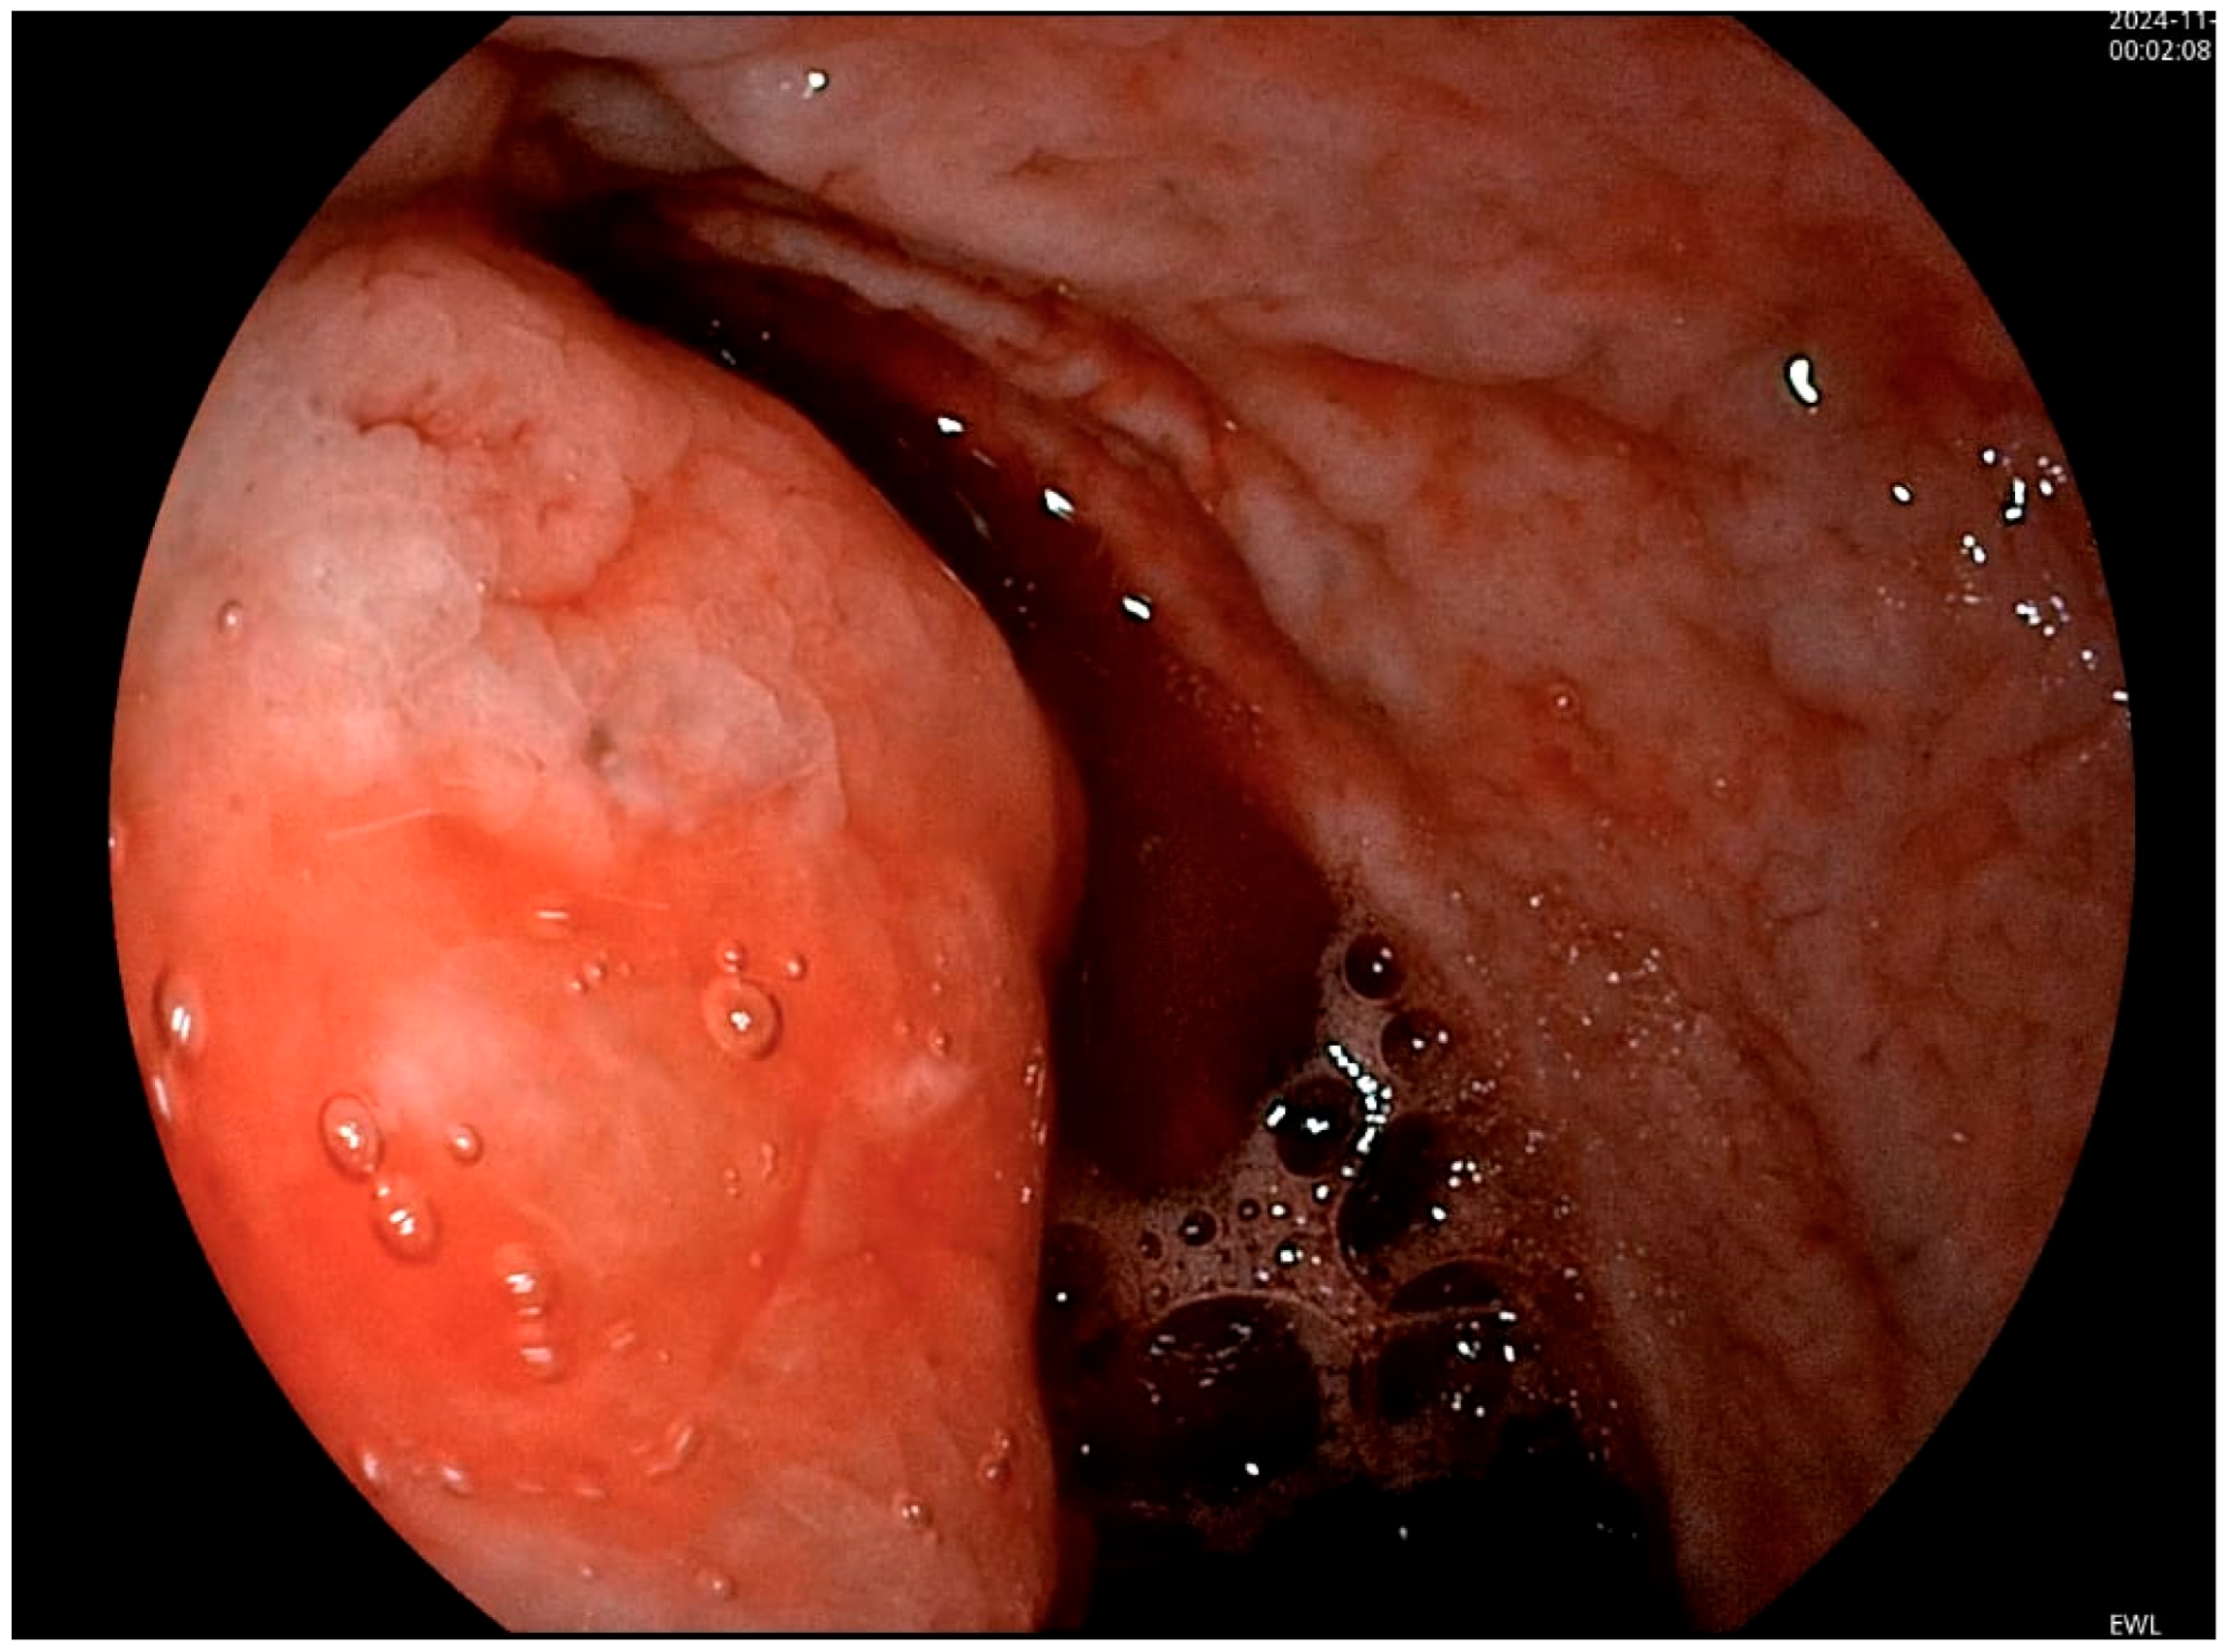

2. Case Presentation